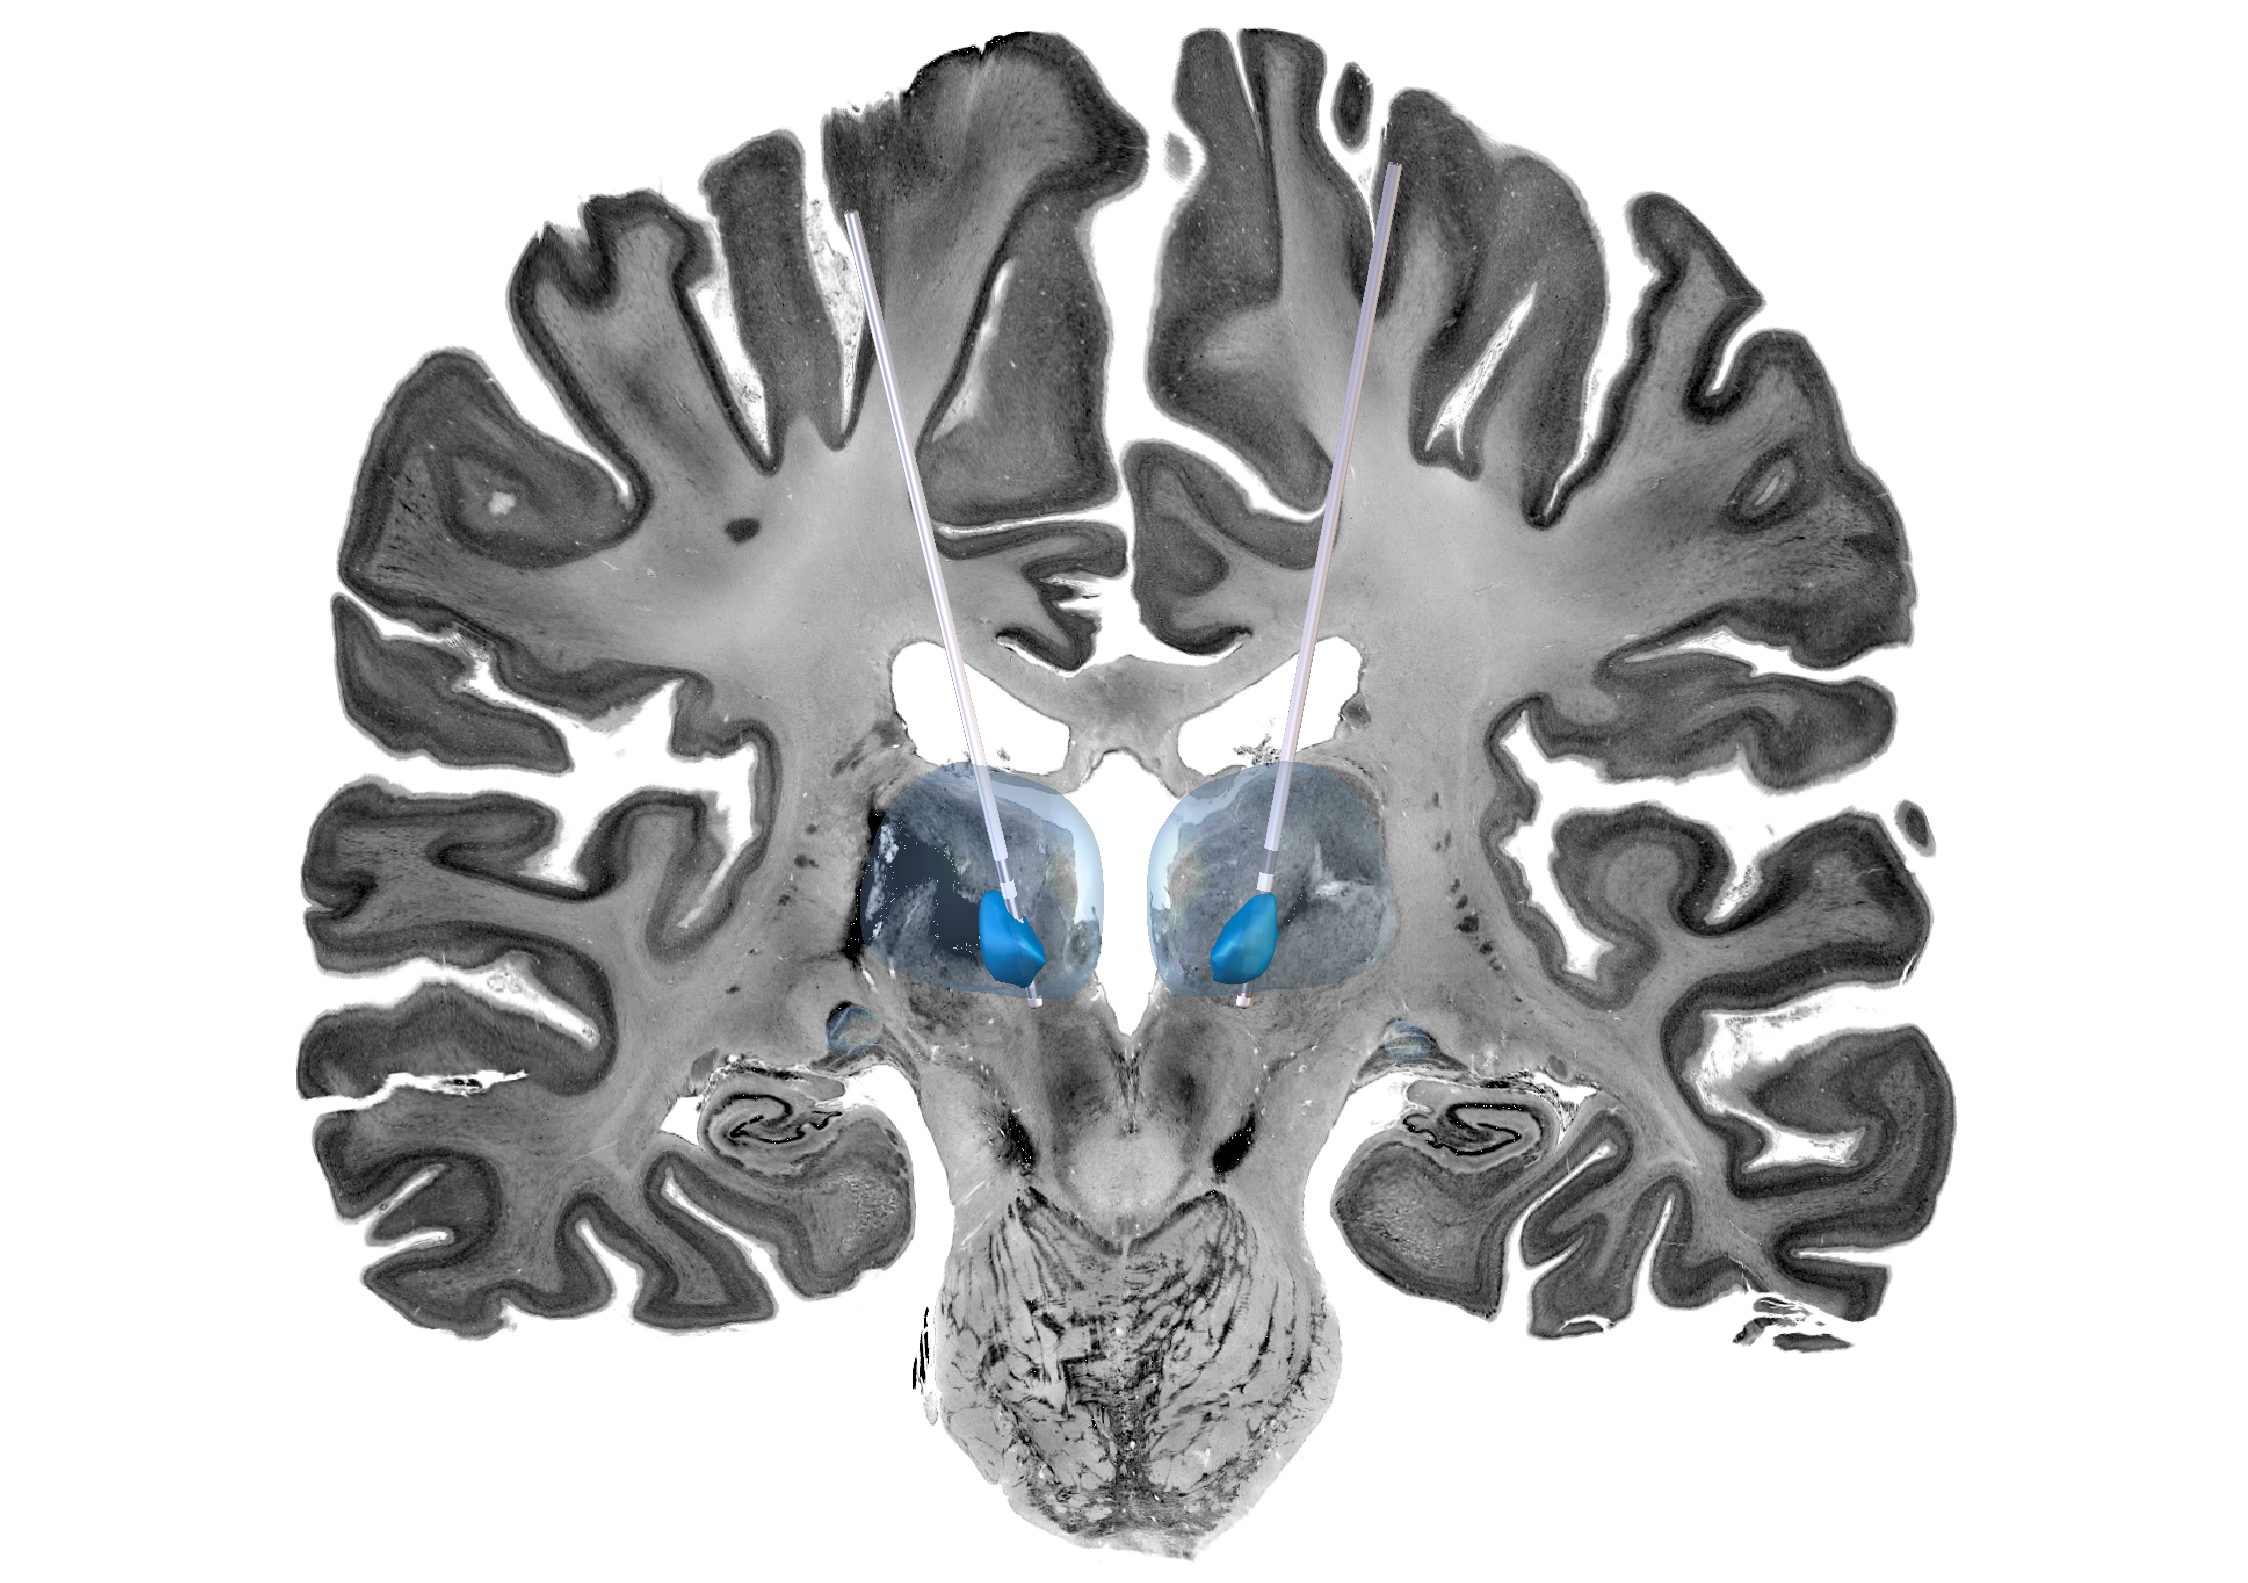

Deep Brain Stimulation (DBS) is a treatment involving surgery to insert a small device which stimulates specific parts of the brain.

Unlike other DBS devices which are mounted on the chest with wires running up the neck to the brain, this device is mounted on the skull meaning the leads are less likely to break or erode as the child grows.

The device targets the thalamus, which is a hub for electrical signals in the brain. It is hoped that the device will block electrical pathways and consequently stop seizures from spreading. The device also has settings for optimisation towards seizure patterns, which although not utilised in this trial, could be used in the future for patients with LGS.